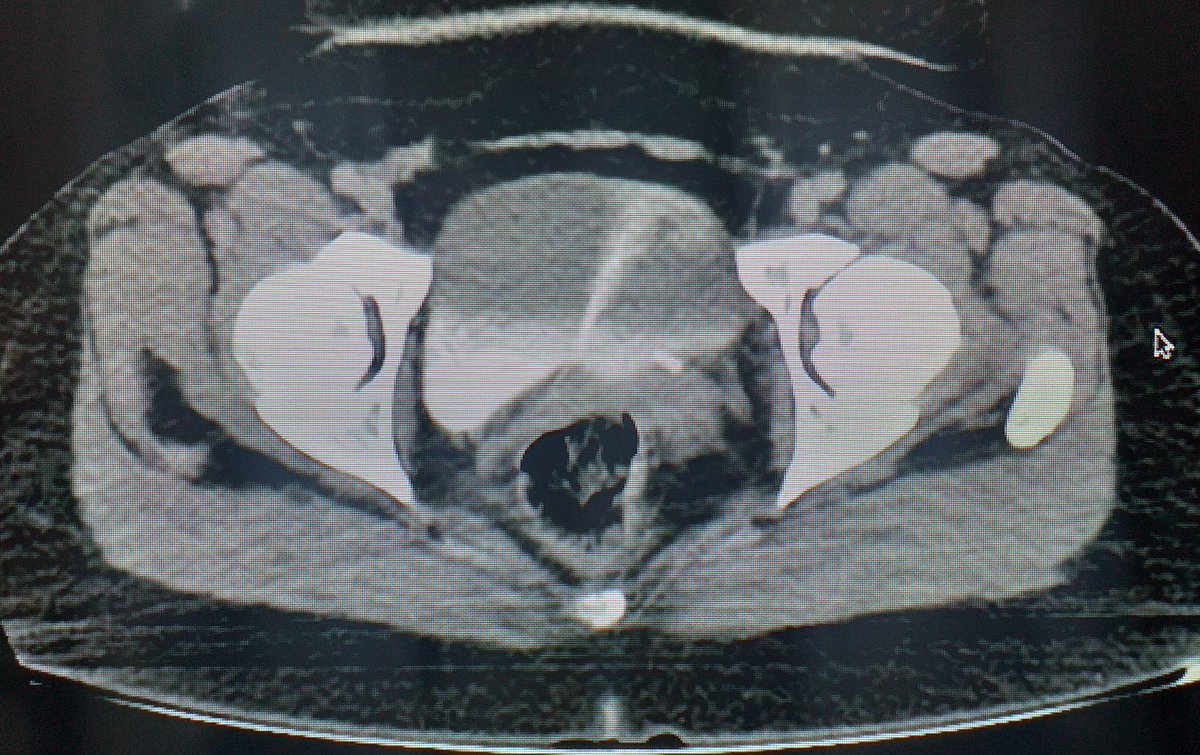

Ureteral JET in CT Scan! ✅⚠️💦 Like a Volcano! 🌋 Or like a Shooting Star 🌠 Maybe like a whale on the sea surface! 🐳 IMAGINATION ... 💭💭💭 Oficina Residentes CAU European Society of Residents in Urology RAEU - Spanish Urology Residents Working Group